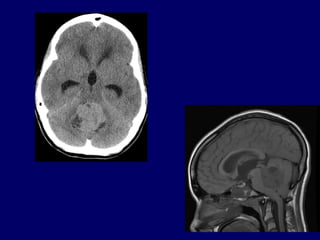

CEREBELO

CEREBELO Regulation of muscle tone, coordinationof skilled voluntary movement Planning and initiation of voluntary activity Maintenance of balance, control of eye movements Vestibulocerebellum Spinocerebellum Cerebrocerebelum Anterior Lobe Posterior Lobe Flocculo-Nodular Lobe (FN lobe) Folia Primary fissure